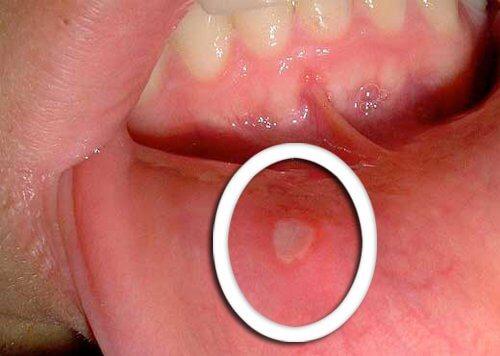

मुंह में आए बदलाव

- ऑरोफरीन्जियल कैंसर का सबसे पहला लक्षण होते हैं ठीक न होने वाले छोटे-छोटे छाले।

- जीभ, मसूड़ों या फ़िर होंठों पर लाल या सफ़ेद निशानों का दिखायी देना भी आम होता है।

- कुछ ही दिनों में ठीक न होने वाले असामान्य बदलावों के प्रति सजग रहते हुए उनके बारे में अपने डॉक्टर को ज़रूर बताएं।